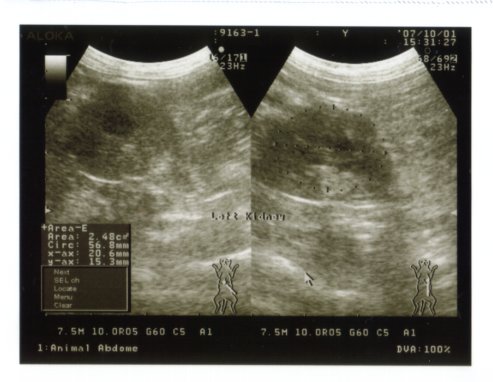

■エコー

・腎臓

右が肥大しており、左はやはり小さく萎縮している(ほぼ機能ははたしていないであろう)

前回(2007/1)から大きさ構造に変化は見られず

がんばって右の腎臓にて維持をしている様子

大切に守ってやらねばならない

左